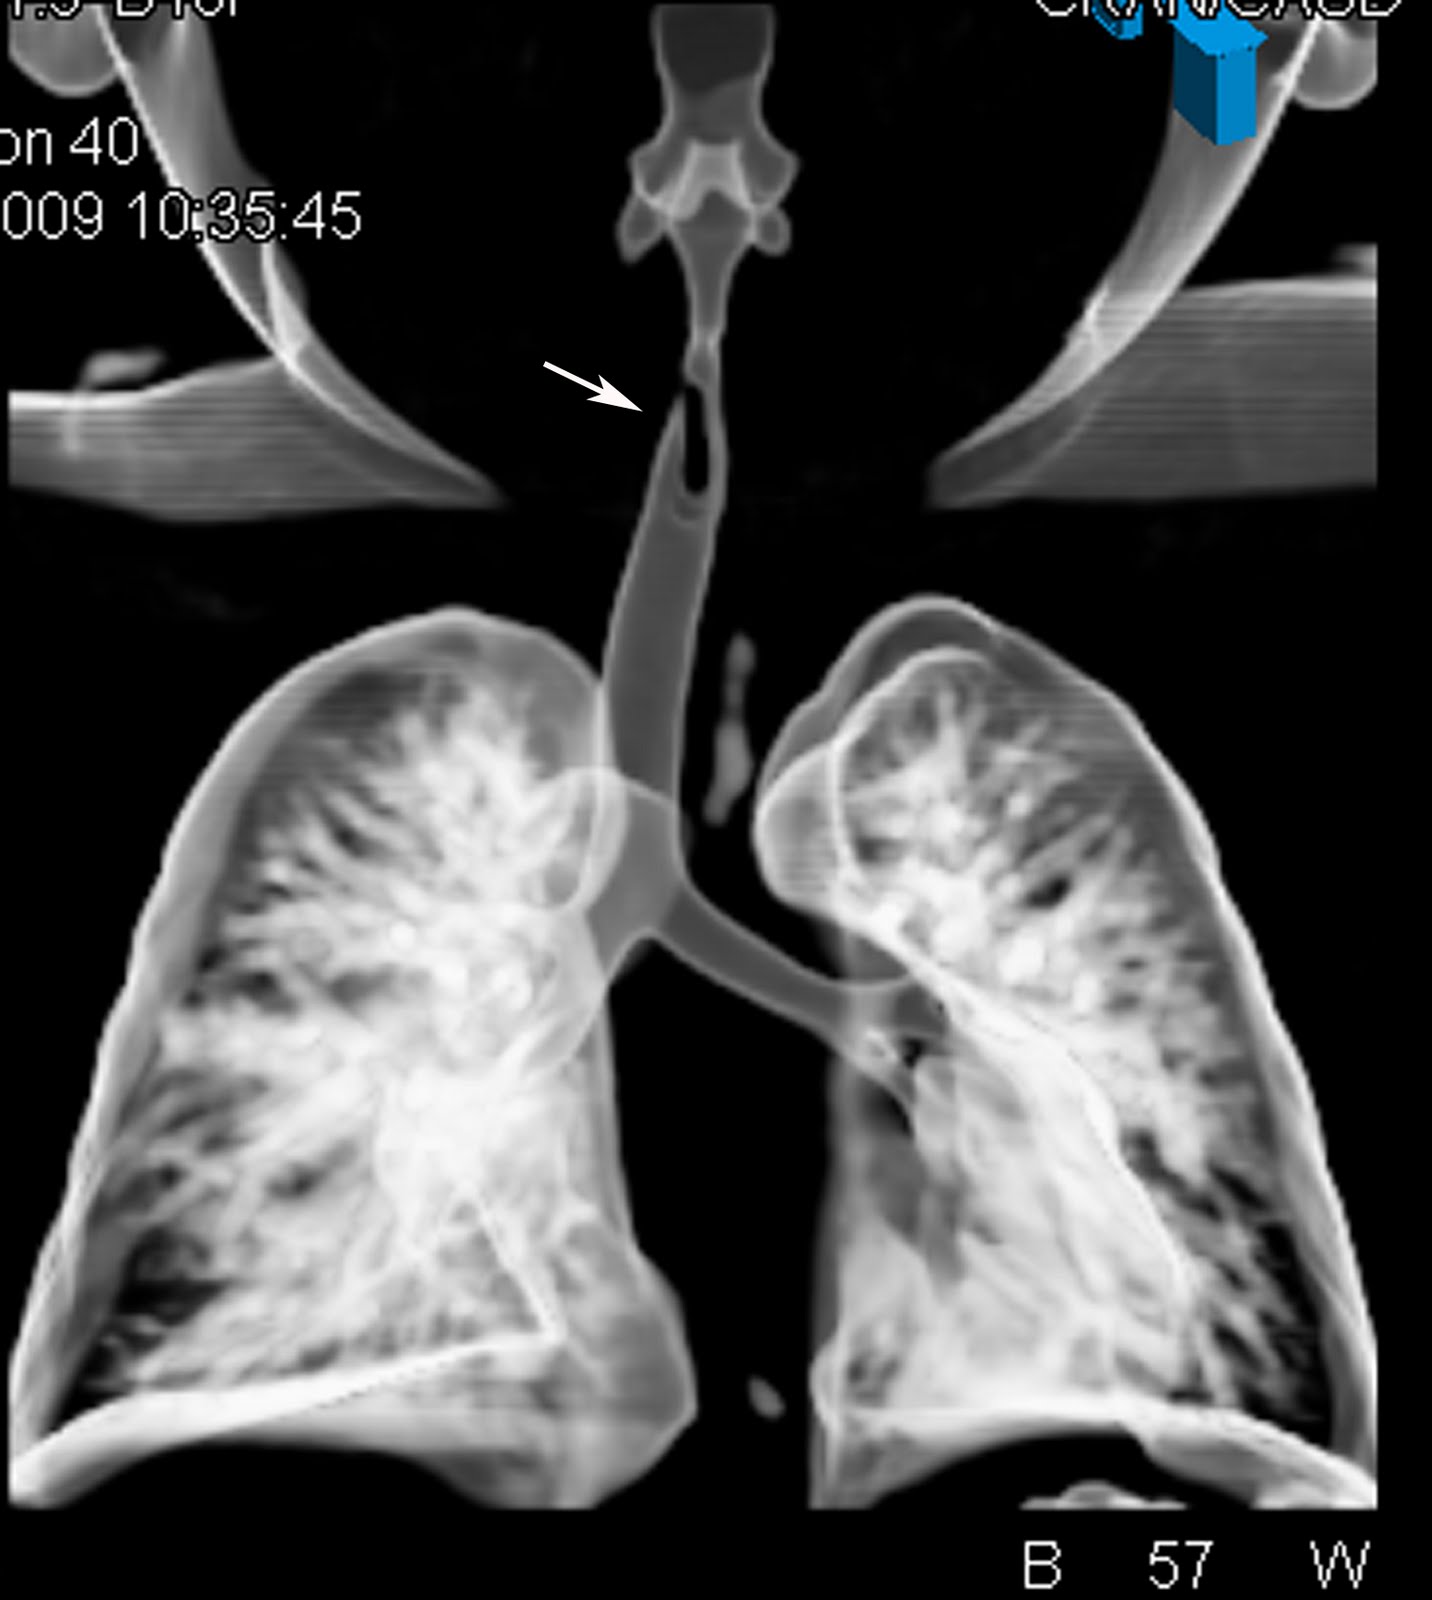

Frontal Xray anteroposterior view showing linear opacity from C4 to

Frontal Xray anteroposterior view showing linear opacity from C4 to Tracheobronchial Foreign Body To compare the clinical and management aspects of tracheobronchial aspirated foreign body (afb) removal in children and adults; Types and location of tracheal and bronchial foreign bodies. Larger objects unable to pass through the larynx can be. The aim of study is to determine epidemiological profile of the cases suspected to have laryngotracheobronchial foreign body,. It is one of the. Tracheobronchial Foreign Body.